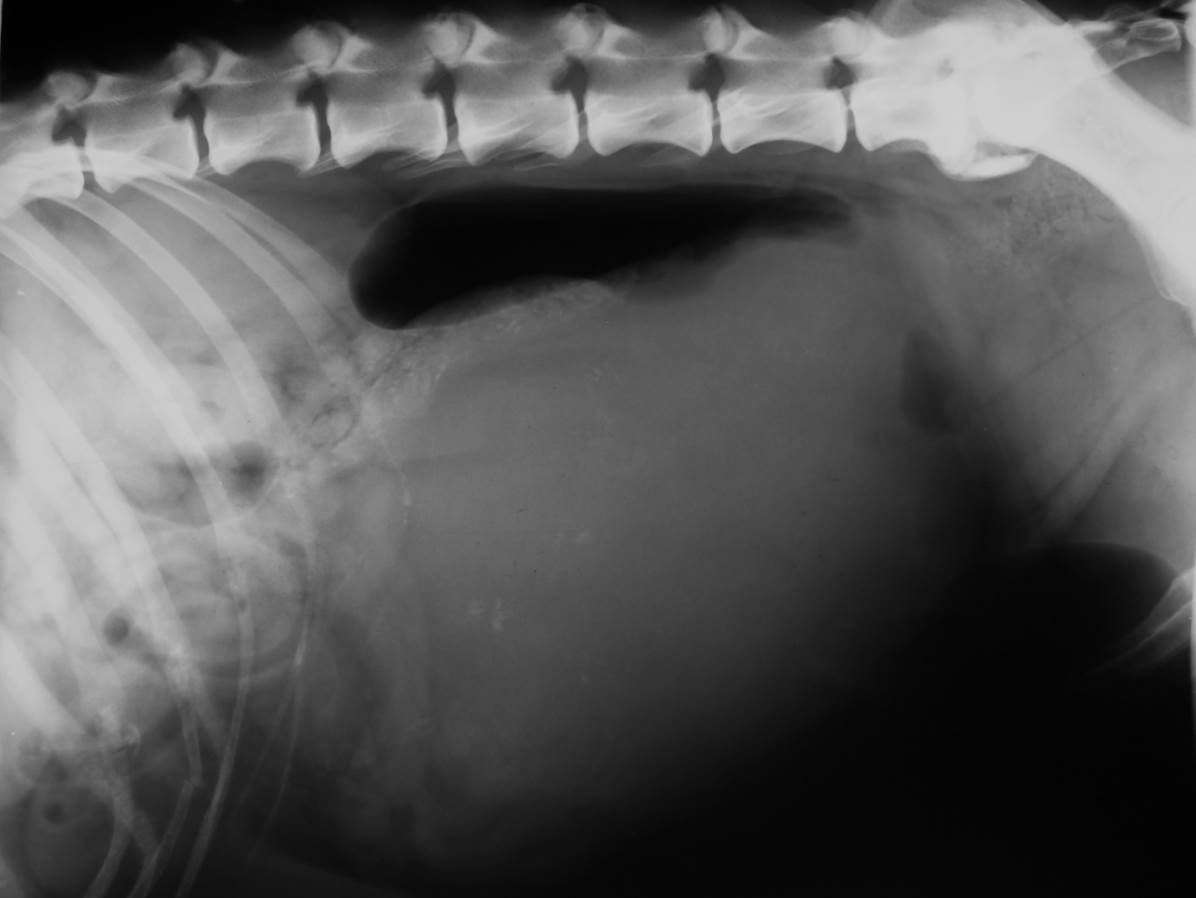

Case Mutley

Discuss this case?